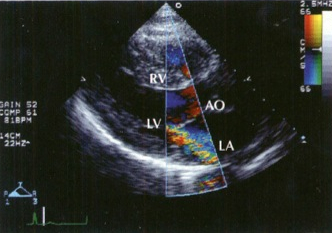

La insuficiencia mitral consiste en el cierre inadecuado de la válvula mitral, lo que condiciona el paso retrógrado de sangre desde el ventrículo hacia la aurícula durante la sístole ventricular.

- Parte del volumen que debería expulsarse a la aorta pasa a la aurícula izquierda. Esto implica un menor gasto cardíaco por un menor volumen sistólico eyectado y conlleva una dilatación tanto de la aurícula izquierda como del ventrículo izquierdo.